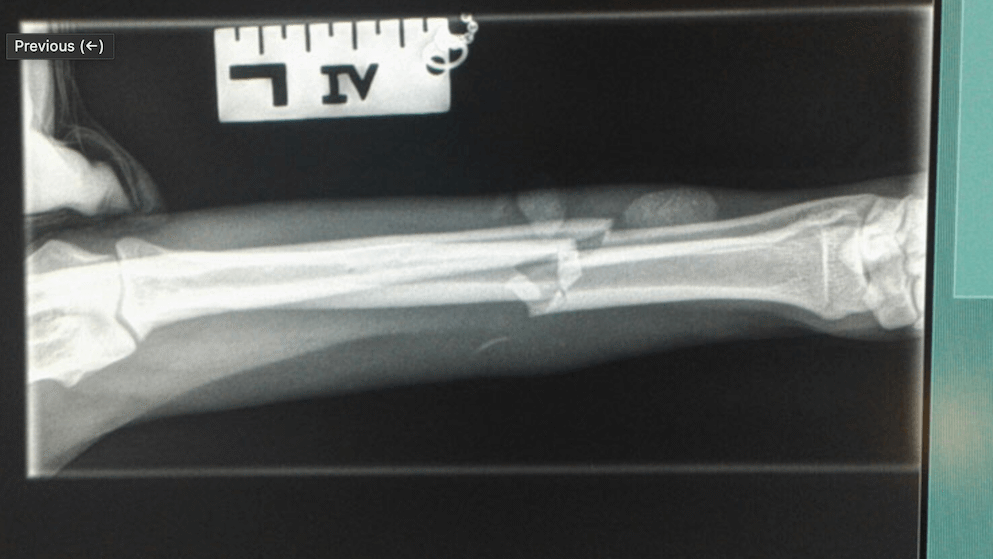

Tibia Fracture Repair

Radius and Ulna Fracture Repair

Example of Minimally Invasive Radius and Ulna Fracture Repair.